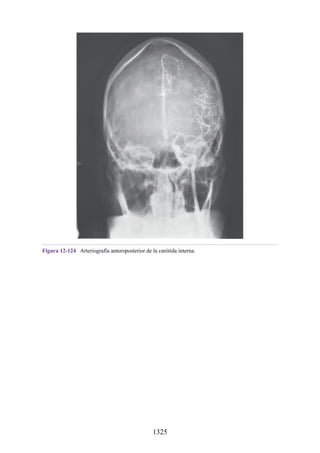

parasimpática

DIVISIÓN SIMPÁTICA